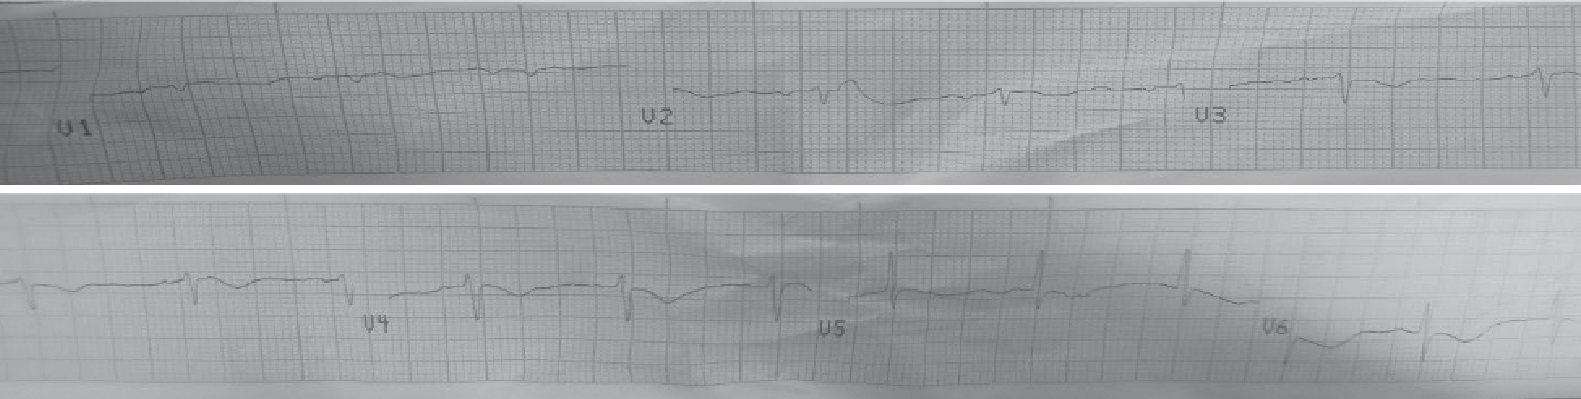

ECG showed T wave inversion from V2 to V6 (Fig. 2). Trop T on the day of admission was 0.4. Both were monitored daily. Trop T initially increased to 0.7 on the second day. But on the fifth day, both ECG (Figs. 3 and 4) and Trop T were normal.

Figure 2. Showing T wave inversion from V2 to V6 (day 1).

Figure 3. Showing T wave inversion reverting to normal (day 3).

Figure 4. Showing T wave inversion reverted to normal (day 5).